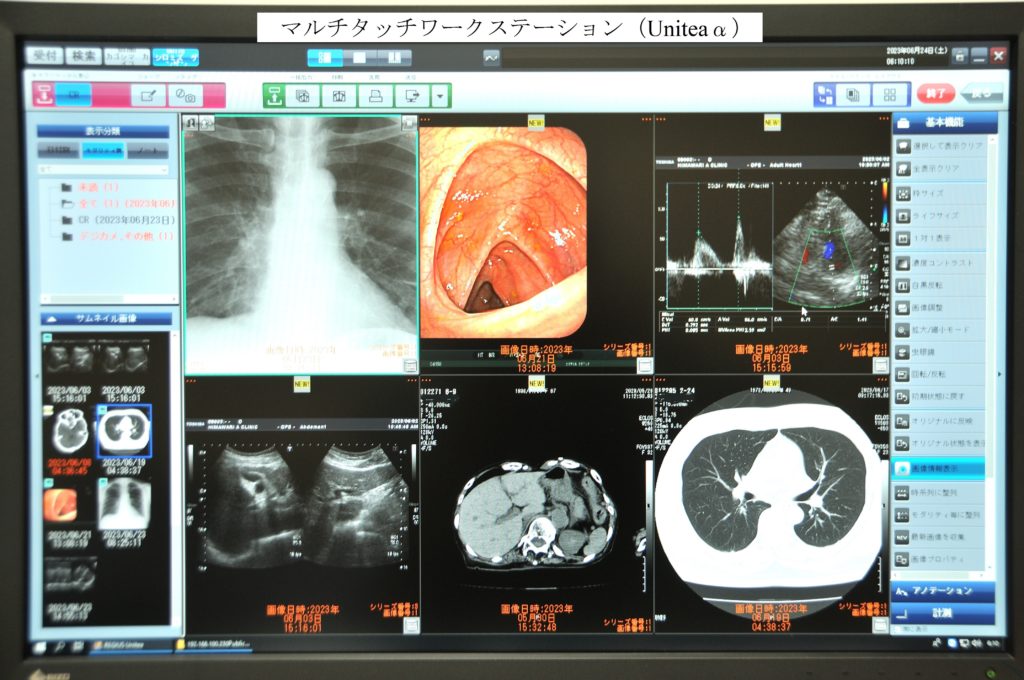

マルチタッチワークステーション(Uniteaα)で、CR画像をはじめ、CT、内視鏡、超音波等とのオンライン接続での画像取り込み、また、汎用メディアやデジカメからの画像取り込みも可能で、全ての画像検査の一元管理が可能です。